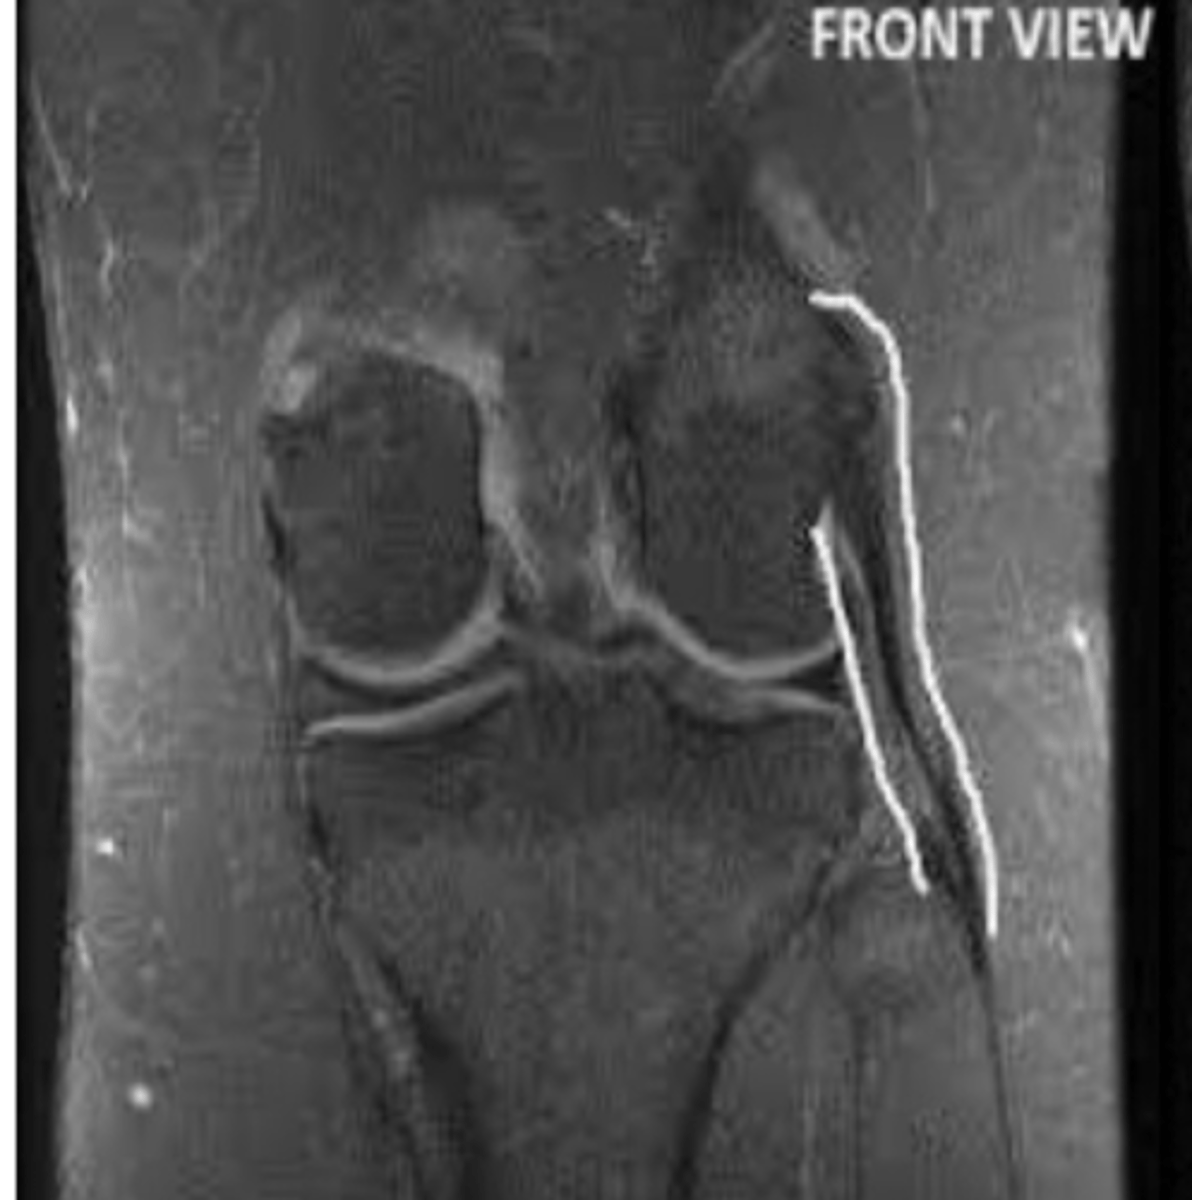

Grade III MCL tear

Define the pathology.